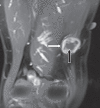

Results: The mean age of the eight patients was 40 (range 27-57) years. The most common presenting feature was a palpable mass. The mean interval between surgical treatment and the onset of clinical symptoms was 17.1 (range 4-72) months. Six of the eight tumours (75.0%) were located in the lower limb, while 2 (25.0%) were located in the upper limb. None of the patients had any preoperative neurological deficits. Tinel's sign was present in one patient. Magnetic resonance (MR) imaging showed that the findings of split-fat sign, low signal margin and fascicular sign were present in all patients. The entry and exit sign was observed in 4 (50.0%) patients, a hyperintense rim was observed in 7 (87.5%) patients and the target sign was observed in 5 (62.5%) patients. All patients underwent microsurgical excision of the tumour and none developed any postoperative neurological deficits.

Conclusion: Intramuscular schwannomas demonstrate the findings of split-fat sign, low signal margin and fascicular sign on MR imaging. These findings are useful for the radiological diagnosis of intramuscular schwannoma.